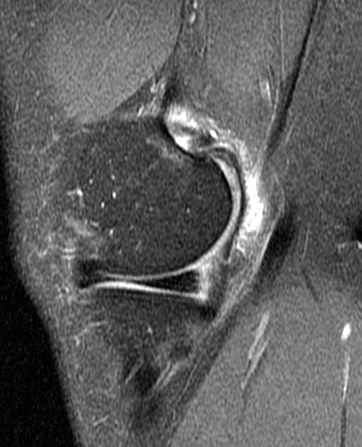

Figure 2 for case Partial tear of the tendon of the medial head of the gastrocnemius muscle ( RID2921 )

Figure 2